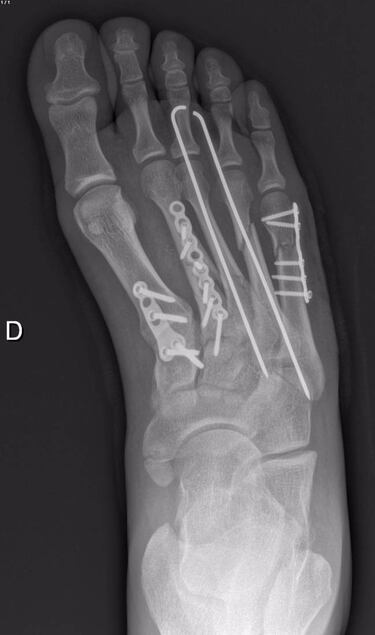

A pesar de que una de las fracturas era más complicada de lo que parecía en un primer momento, los médicos pudieron llevar a cabo su trabajo en hora y media, fijando las fracturas con tres placas de titanio, dos clavos y quince tornillos. Está visto que material tiene para montar una ferretería pero, bromas al margen, lo importante es que el piloto de 23 años ha recibido el alta médica hoy, pero no será hasta dentro de una semana cuando pueda comenzar la rehabilitación con fisioterapia.